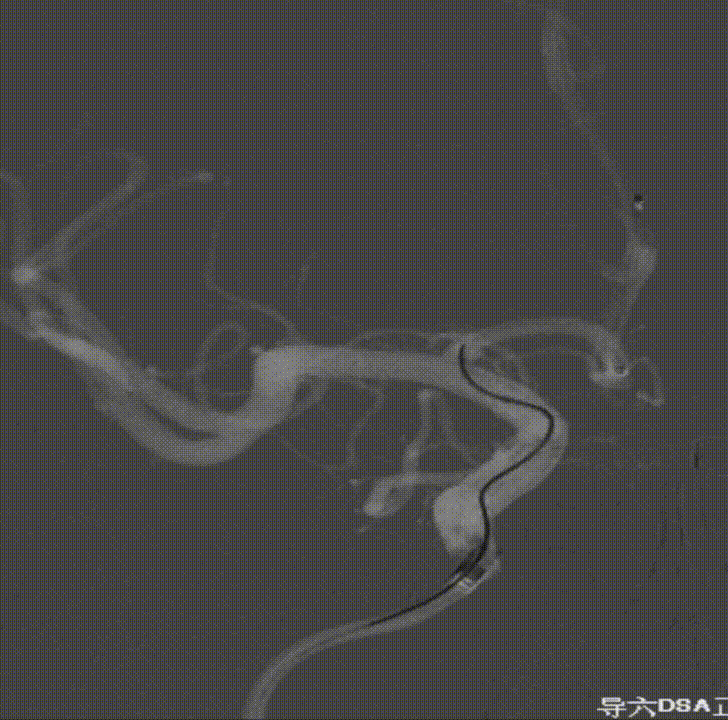

撤出弹簧圈,Asahi 0.014微导丝引导璞慧 0.017微导管穿支架网孔进入动脉瘤内。

继续填入Target 1.5/2弹簧圈成篮,后完全释放支架,其近端位于颈内动脉分叉处,远端位于A1远端。

填入第一枚弹簧圈

通过调整栓塞微导管的张力继续填入Target 1/3弹簧圈。